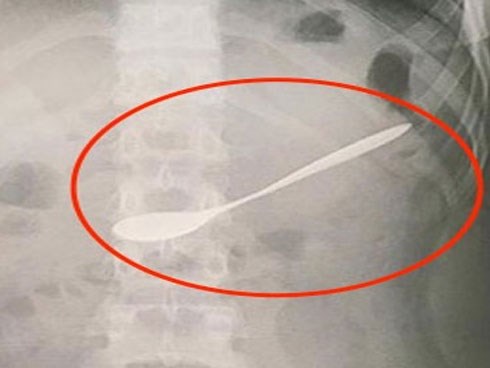

Uống cà phê, cô gái nuốt chửng thìa vào bụng

Trong lúc uống cà phê bằng thìa, cô gái không may bị bạn thúc vào tay làm nuốt luôn chiếc thìa vào bụng.